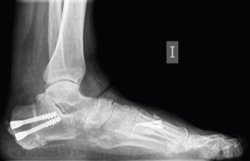

Figura 10. Radiografía en carga a los 2 meses de la cirugía.

Los procedimientos que acompañan a la OCP en la corrección de las deformidades suelen marcar el tiempo de descarga e inmovilización. Cuando la osteotomía es el único procedimiento óseo de la corrección, se autoriza una carga protegida con bota de tipo Walker e inicio de ejercicios de flexoextensión de tobillo a las 4-5 semanas, para posteriormente iniciar progresivamente la carga completa 2 semanas después (Figuras 10 y 11).

Figura 11. Detalle de la osteotomía en la tomografía computarizada a los 3 meses.